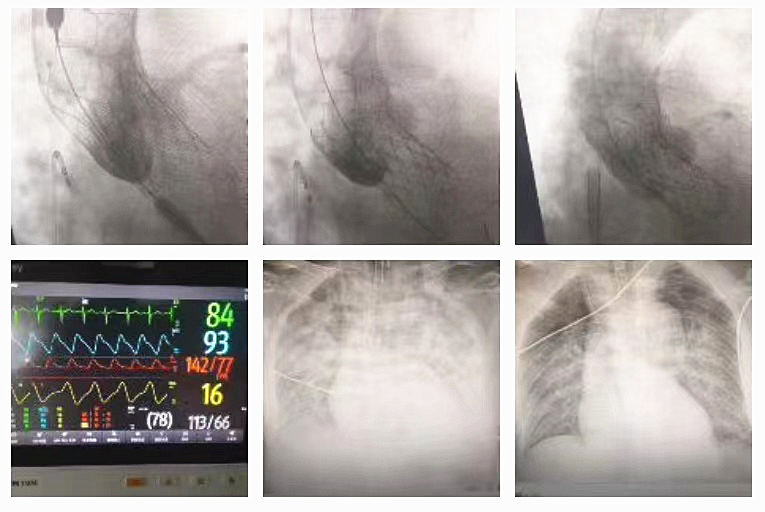

黄阿姨因主动脉瓣狭窄引起胸闷、气促而入院。胸心血管外科黄小龙充分评估患者病情,完善心脏彩超、主动脉CTA等相关检查,结果提示患者的主动脉瓣中度狭窄合并重度关闭不全,瓣膜及瓣环严重钙化,需要进行置换心脏瓣膜。在多科联合团队紧密默契的配合下,成功为患者行经导管主动脉瓣置换术(TAVR),术后患者血压和心率恢复到正常状态,手术用时短,患者胸闷、气促症状及各项指标得到了明显的好转,术后恢复良好,顺利康复出院。

医师节这天,胸心血管外科团队成功为一名主动脉层 Standord B型患者在全麻下施行胸主动脉覆膜支架植入术,手术顺利完成,用时短,效果好,一周后顺利出院。心血管外科主任黄小龙表示:这是今年医师节最好的礼物!

57岁的刘先生,三个月前反复出现活动后胸闷气喘,检查发现患有二尖瓣关闭不全、三尖瓣关闭不全等症状,胸心血管外科团队为患者实施了体外循环下二尖瓣、三尖瓣置换术,术后患者生命体征平稳,恢复良好。

一名年仅38岁的小莫,因为上腹部急性撕裂样疼痛被紧急送往我院,急诊CT提示A型主动脉夹层。为了患者术后的高质量生活,避免终身抗凝及二次手术,胸心血管外科团队经过反复讨论与评估,最终选择手术难度超高的David方式处理,在团队的努力下,为小莫进行了David+孙氏手术,手术顺利完成!